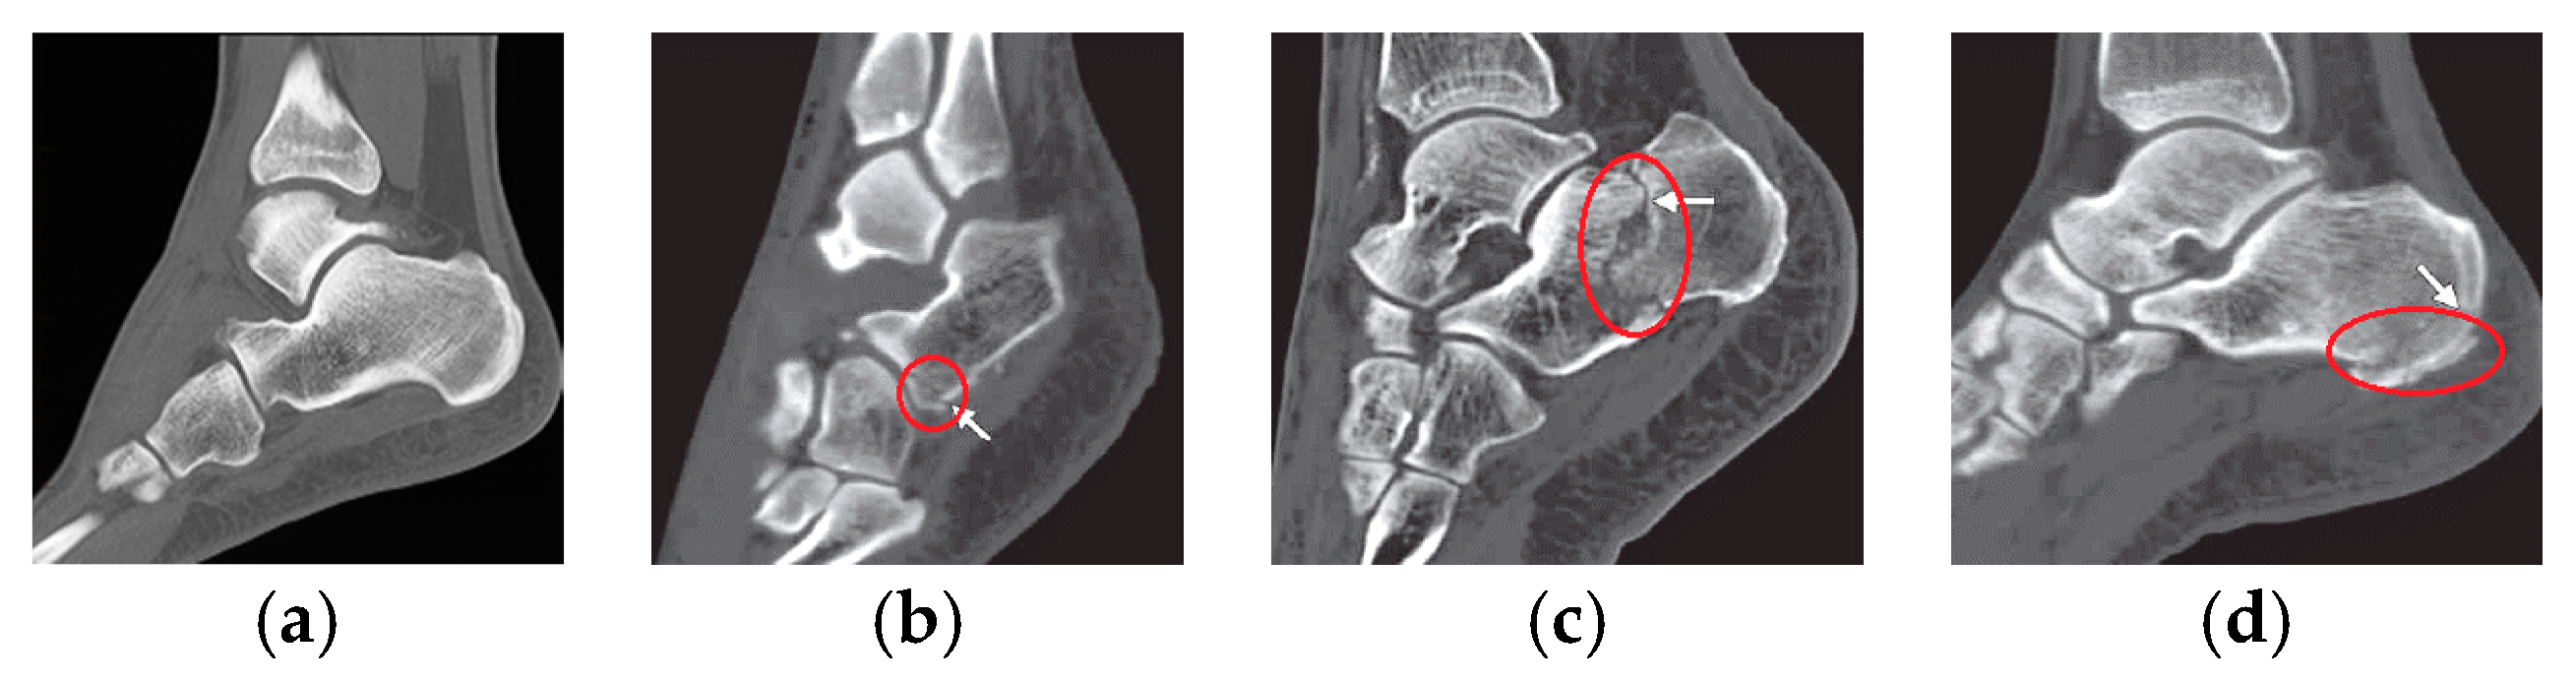

Sanders classification of calcaneal fractures in CT images with deep Sanders Classification Of Calcaneal Fractures Although widely used since its introduction in 1993, the sanders classification has several noted limitations. Calcaneus fractures are the most common fractured tarsal bone and are associated with a high degree of morbidity and disability. The classification was published in 1992 and it. • describe the classification systems of calcaneal fractures • understand how patient, injury, and surgeon factors affect. Sanders Classification Of Calcaneal Fractures.